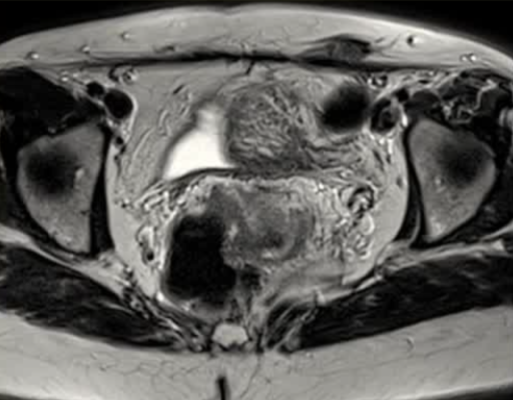

| 腹壁下病变 | MRI引导下 冷冻消融。装有热水的手套在皮肤表面保护皮肤 |

通常需要三根布针

保护措施:几乎所有干预都需要辅助保护措施,其中水分离术(13/16,81.3%)和水分离术与温盐水填充手套的皮肤保护结合(9/16,56.3%)是最常见的保护措施。